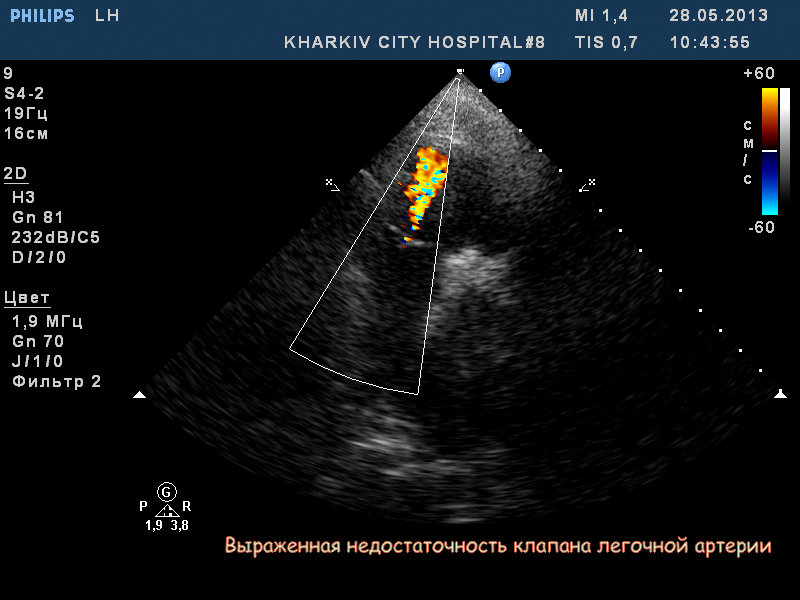

Пациентка 83 лет. Жалобы на сильную одышку в теч. последнего месяца.

кальциноз створок АК, дилатация левого предсердия, правых полостей, выраженная недостаточность ТК и клапана ЛА, гипертрофия левого желудочка. Дополнительные косые хорды левого желудочка. Высокая ЛГ (АТ/ЕТ- 0.20 Рсред. ЛА-69мм рт.ст.).